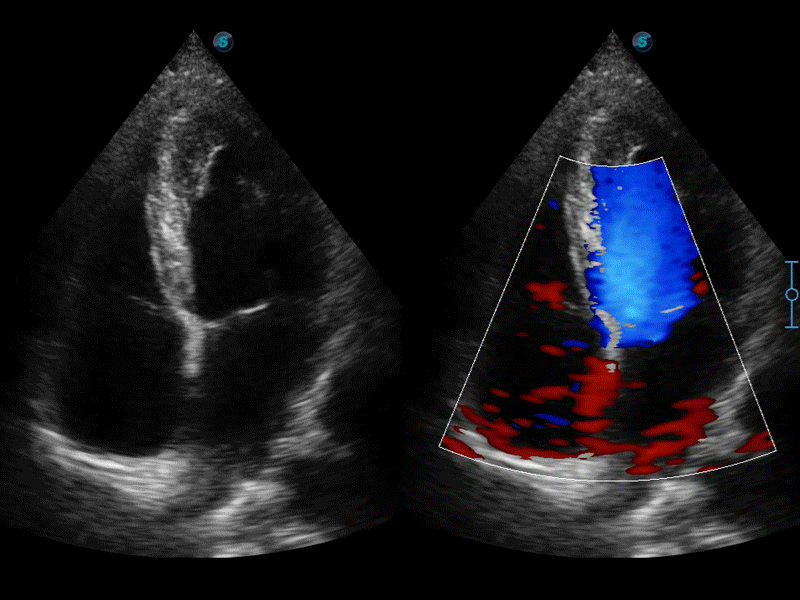

高分辨率血流成像技術(shù)提高了對(duì)低速血流信號(hào)的檢測(cè)能力。在提高空間分辨率的同時(shí),也克服了血流外溢現(xiàn)象,為用戶提供更加真實(shí)的血流動(dòng)力學(xué)信息。

通過(guò)色彩血流和實(shí)時(shí)寬景相結(jié)合,可觀察到完整的靜脈或動(dòng)脈的血流,方便醫(yī)生檢查。實(shí)時(shí)掃查過(guò)程中,如有任何操作失誤也可以很容易地進(jìn)行回掃擦除,而不會(huì)中斷掃查。